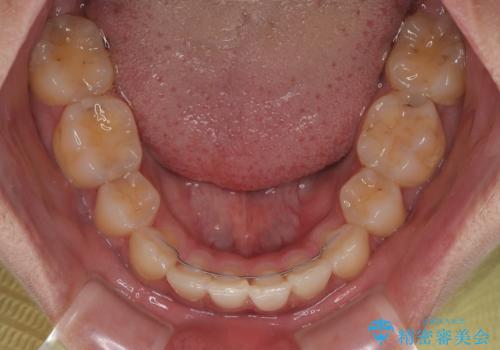

- 高校生の時に行った抜歯矯正の後戻りを気にして来院された患者様です。

インビザラインでの治療を希望されていて、デコボコの程度が中等度であり、安価なパッケージにて対応可能と判断されたため、インビザライン・モデレートを用いて矯正治療を行うこととしました。

インビザライン・モデレートは、製作できるアライナーの枚数に制限があるため、移動可能な量に限りがあるものの、インビザライン・ライトよりも枚数が多いため、幅広い症例に対応可能です。